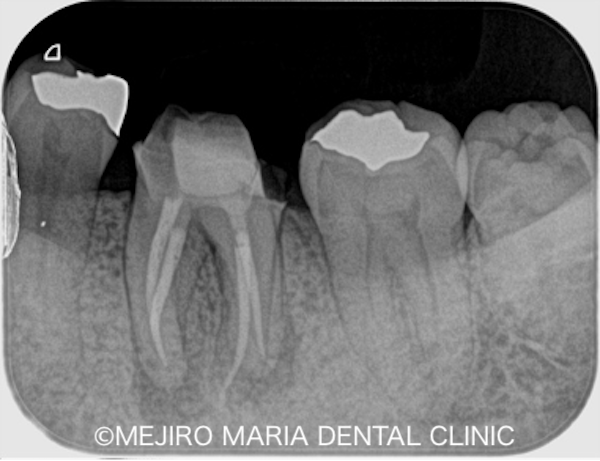

詰め物(メタルインレー)を除去すると歯は虫歯によって軟化しており、容易に歯髄腔まで到達することができました。(写真1)。顕微鏡下でう蝕検知液を使用して虫歯(軟化象牙質)を完全に除去し(写真2)、コンセプトに沿って根管治療を開始しました(写真3)。

今回治療した下顎第二大臼歯の根は、近心根と遠心根という2つの根に分かれています。融合して1つの根になっている場合が多いですが、約3割の確率で、2つに分かれているとされています。さらに近心根は細く湾曲していることが多いため、根管治療は慎重かつ正確に行う必要があります。